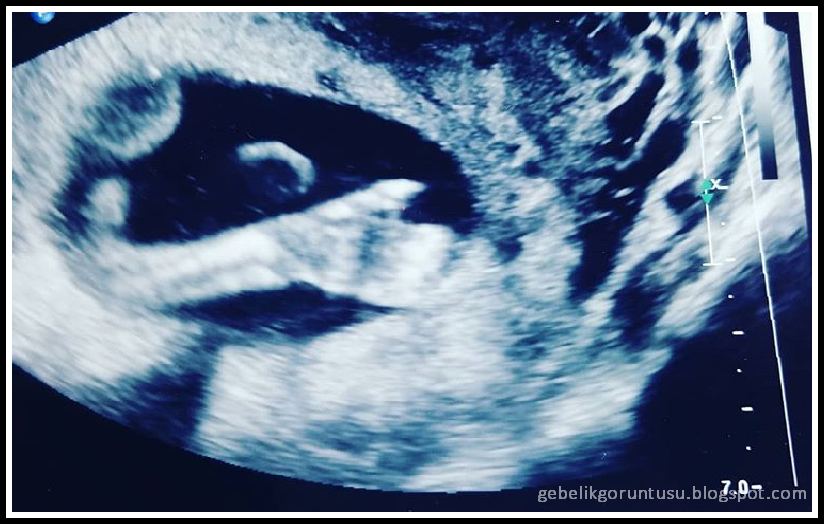

18 Haftalık Gebelik (Hamilelik) Ultrason Görüntüleri

18 Haftalık Gebelik (Hamilelik)

18 haftalık gebelik ultrason görüntüleri